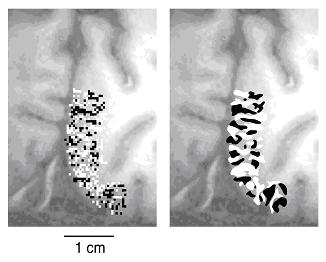

ヒトの第一次視覚野は、大脳半球後頭葉の内側面で前後に伸びる鳥矩溝(ちょうくこう)と呼ばれる溝に沿って広がっている。脳の詳細な形は、人ごとにかなり違うが、多くの人で、鳥矩溝の上下の壁に広がる大脳皮質の部分は比較的平らである。そこで、イメージングのスライス面が鳥矩溝の上壁または下壁のなるべく広い範囲で大脳皮質と完全に重複するように、イメージングのスライス面の傾きと位置を個々の被験者で調節した。白黒のチェッカーボードのようなパターンを1秒間に8回白黒反転する視覚刺激を、光ファイバーの束を通して片方ずつの目の網膜に投影した。左目刺激の間の機能的イメージと右目刺激の間の機能的イメージを比較することによりストライプ状のパターンが得られた(図)。このパターンはサルの眼優位性コラムと同じように、ストライプを構成し、帯の長軸方向は第一次視覚野の境界(大脳半球の内側表面にあり、鳥矩溝が内側表面に出る縁にほぼ平行に走る)にほぼ垂直であった。一方、ひとつずつのコラムの幅は平均して1ミリであり、サルのそれの約2倍であった。